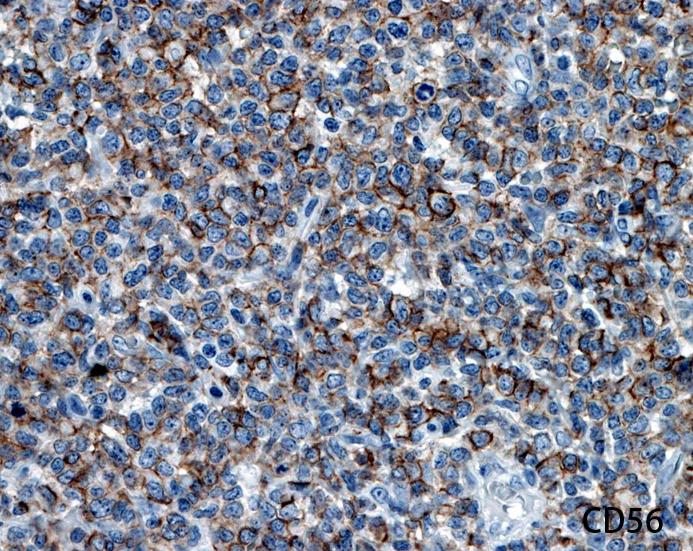

CD56.jpg

CD56CD123TdT